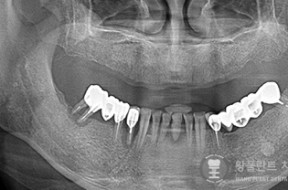

전후사례